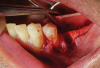

The patient received amoxicillin 500 mg 3 times a day for 10 days, starting the day before surgery.13,14 A full-thickness flap was elevated, extending from tooth No. 22 to at least one tooth mesial and distal to the mesh placement area (Figure 3). Although a vertical releasing incision was not necessary mesially, one can be made to allow sufficient tissue and ensure tension-free closure. It is important that the vertical incision does not end at the joint between the host bone and mesh. The periosteum in this case was left intact and no superficial release of the mylohyoid lingual was necessary.3,15,16

Fig 3. Premolar extracted and flap release.

Figure 3